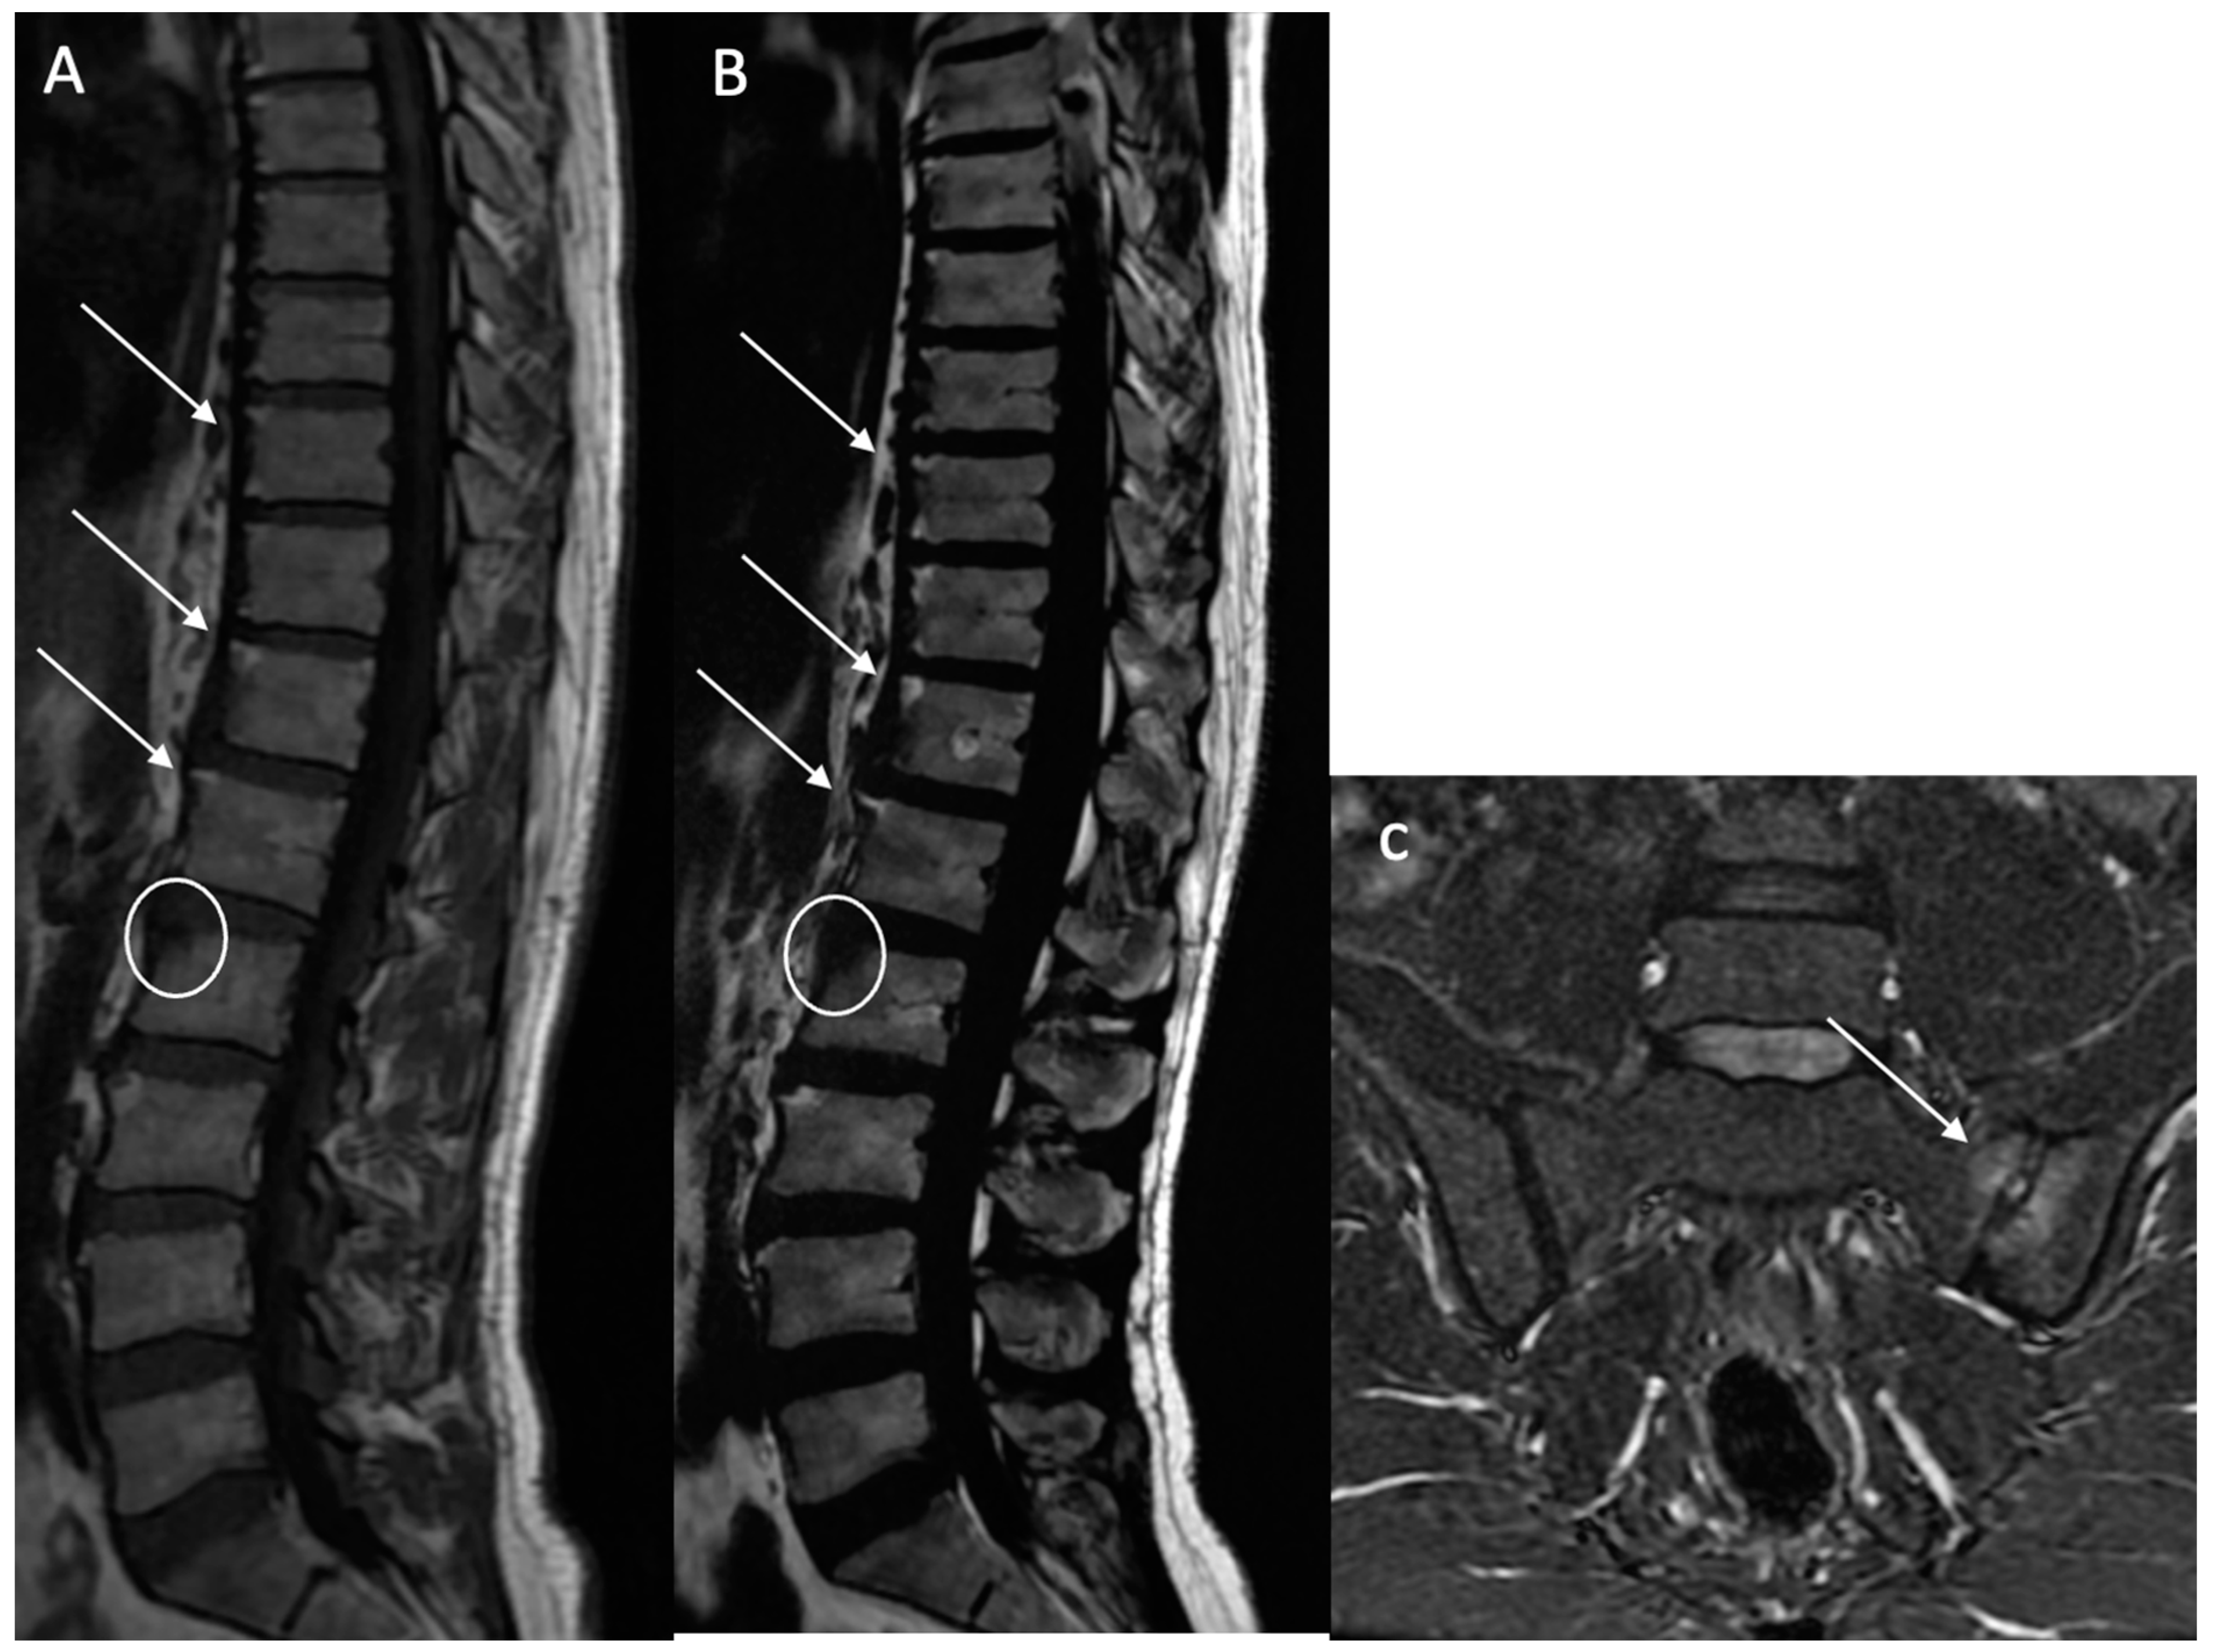

Structural erosions (BMEs): Defined as focal and ill-defined enthesis cortical defects that could be isolated or confluent, with a loss of the normal subchondral cortex appearance and broad irregular margins on both sequences (Figure 3).

Figure 3. Multiple fatty lesion (BMF) changes and erosions in a 61-year-old patient. A T1w sagittal sequence showing BMF localization mainly at the thoracic longitudinal ligamentary structure enthesis (arrows) (A). Focal erosion is noted at the L4 and L5 anterosuperior vertebral corner (circle), and appears as a focal hyposignal. A T2w Dixon (fat) image more clearly showing BMF localization (arrows). Erosion areas are surrounded by fatty replacement areas (B). A T2w STIR coronal oblique sequence showing left anterior inflammatory sacroiliitis (C). A T1w coronal oblique sequence showing structural changes with an erosive sacroiliac lesion (D).